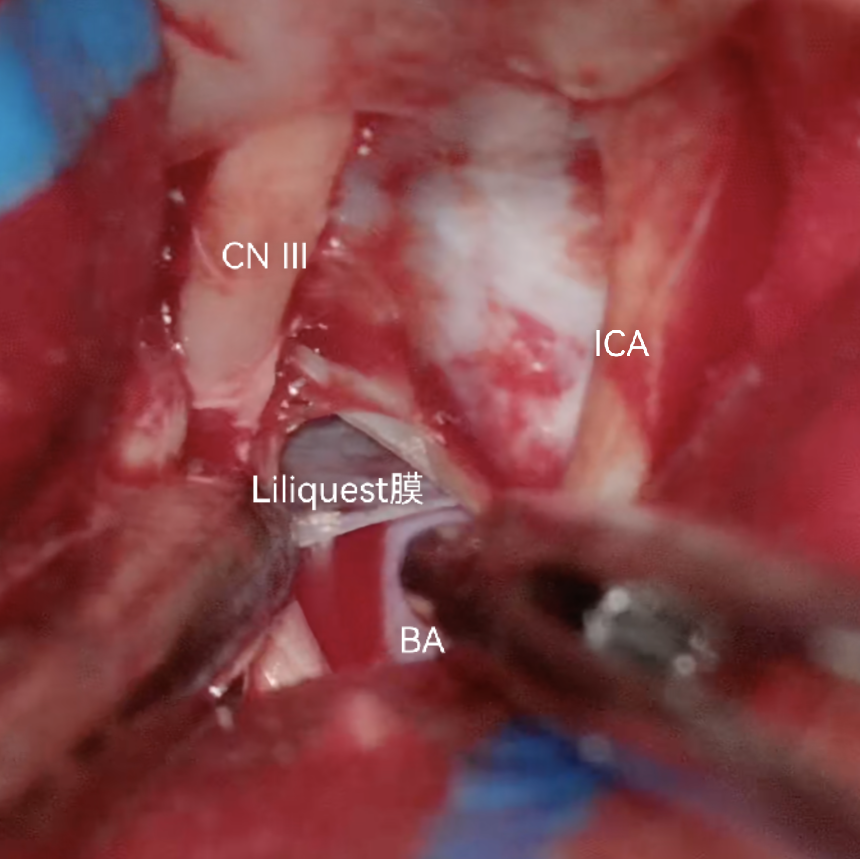

向后探查三间隙和动眼神经

经第三间隙剪开Liliquest膜

经第三间隙显露基底动脉